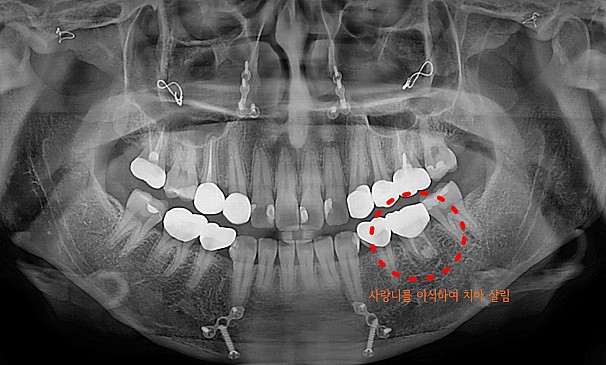

자가치아이식술란?

도저히 살릴 수 없는 치아를 뽑고 그 자리에 자신의 사랑니를 이식하는 치료방법입니다.

기능이 없는 사랑니를 이동하여 이식함으로써 내 자연치아를 사용할 수 있습니다.

자가치아이식술

박OO님 전후사진 | 치료 기간 : 1주

치료 전